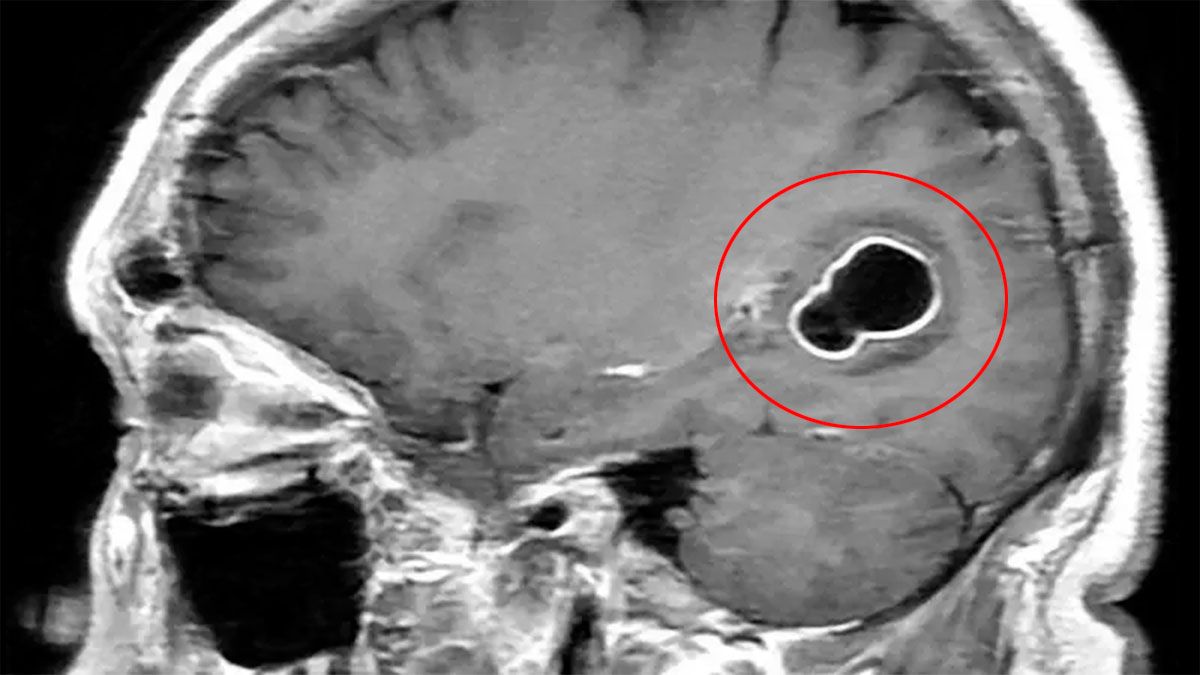

Al realizarle tomografías, los médicos encontraron la presencia de numerosos quistes en el cerebro que, según luego comprobaron con estudios posteriores, en realidad eran larvas de tenia que se habían instalado en su cerebro y que eran las causantes de una infección conocida como neurocisticercosis.

Esta infección es causada por las larvas del parásito Taenia solium (T.solium), también conocido como tenia del cerdo.